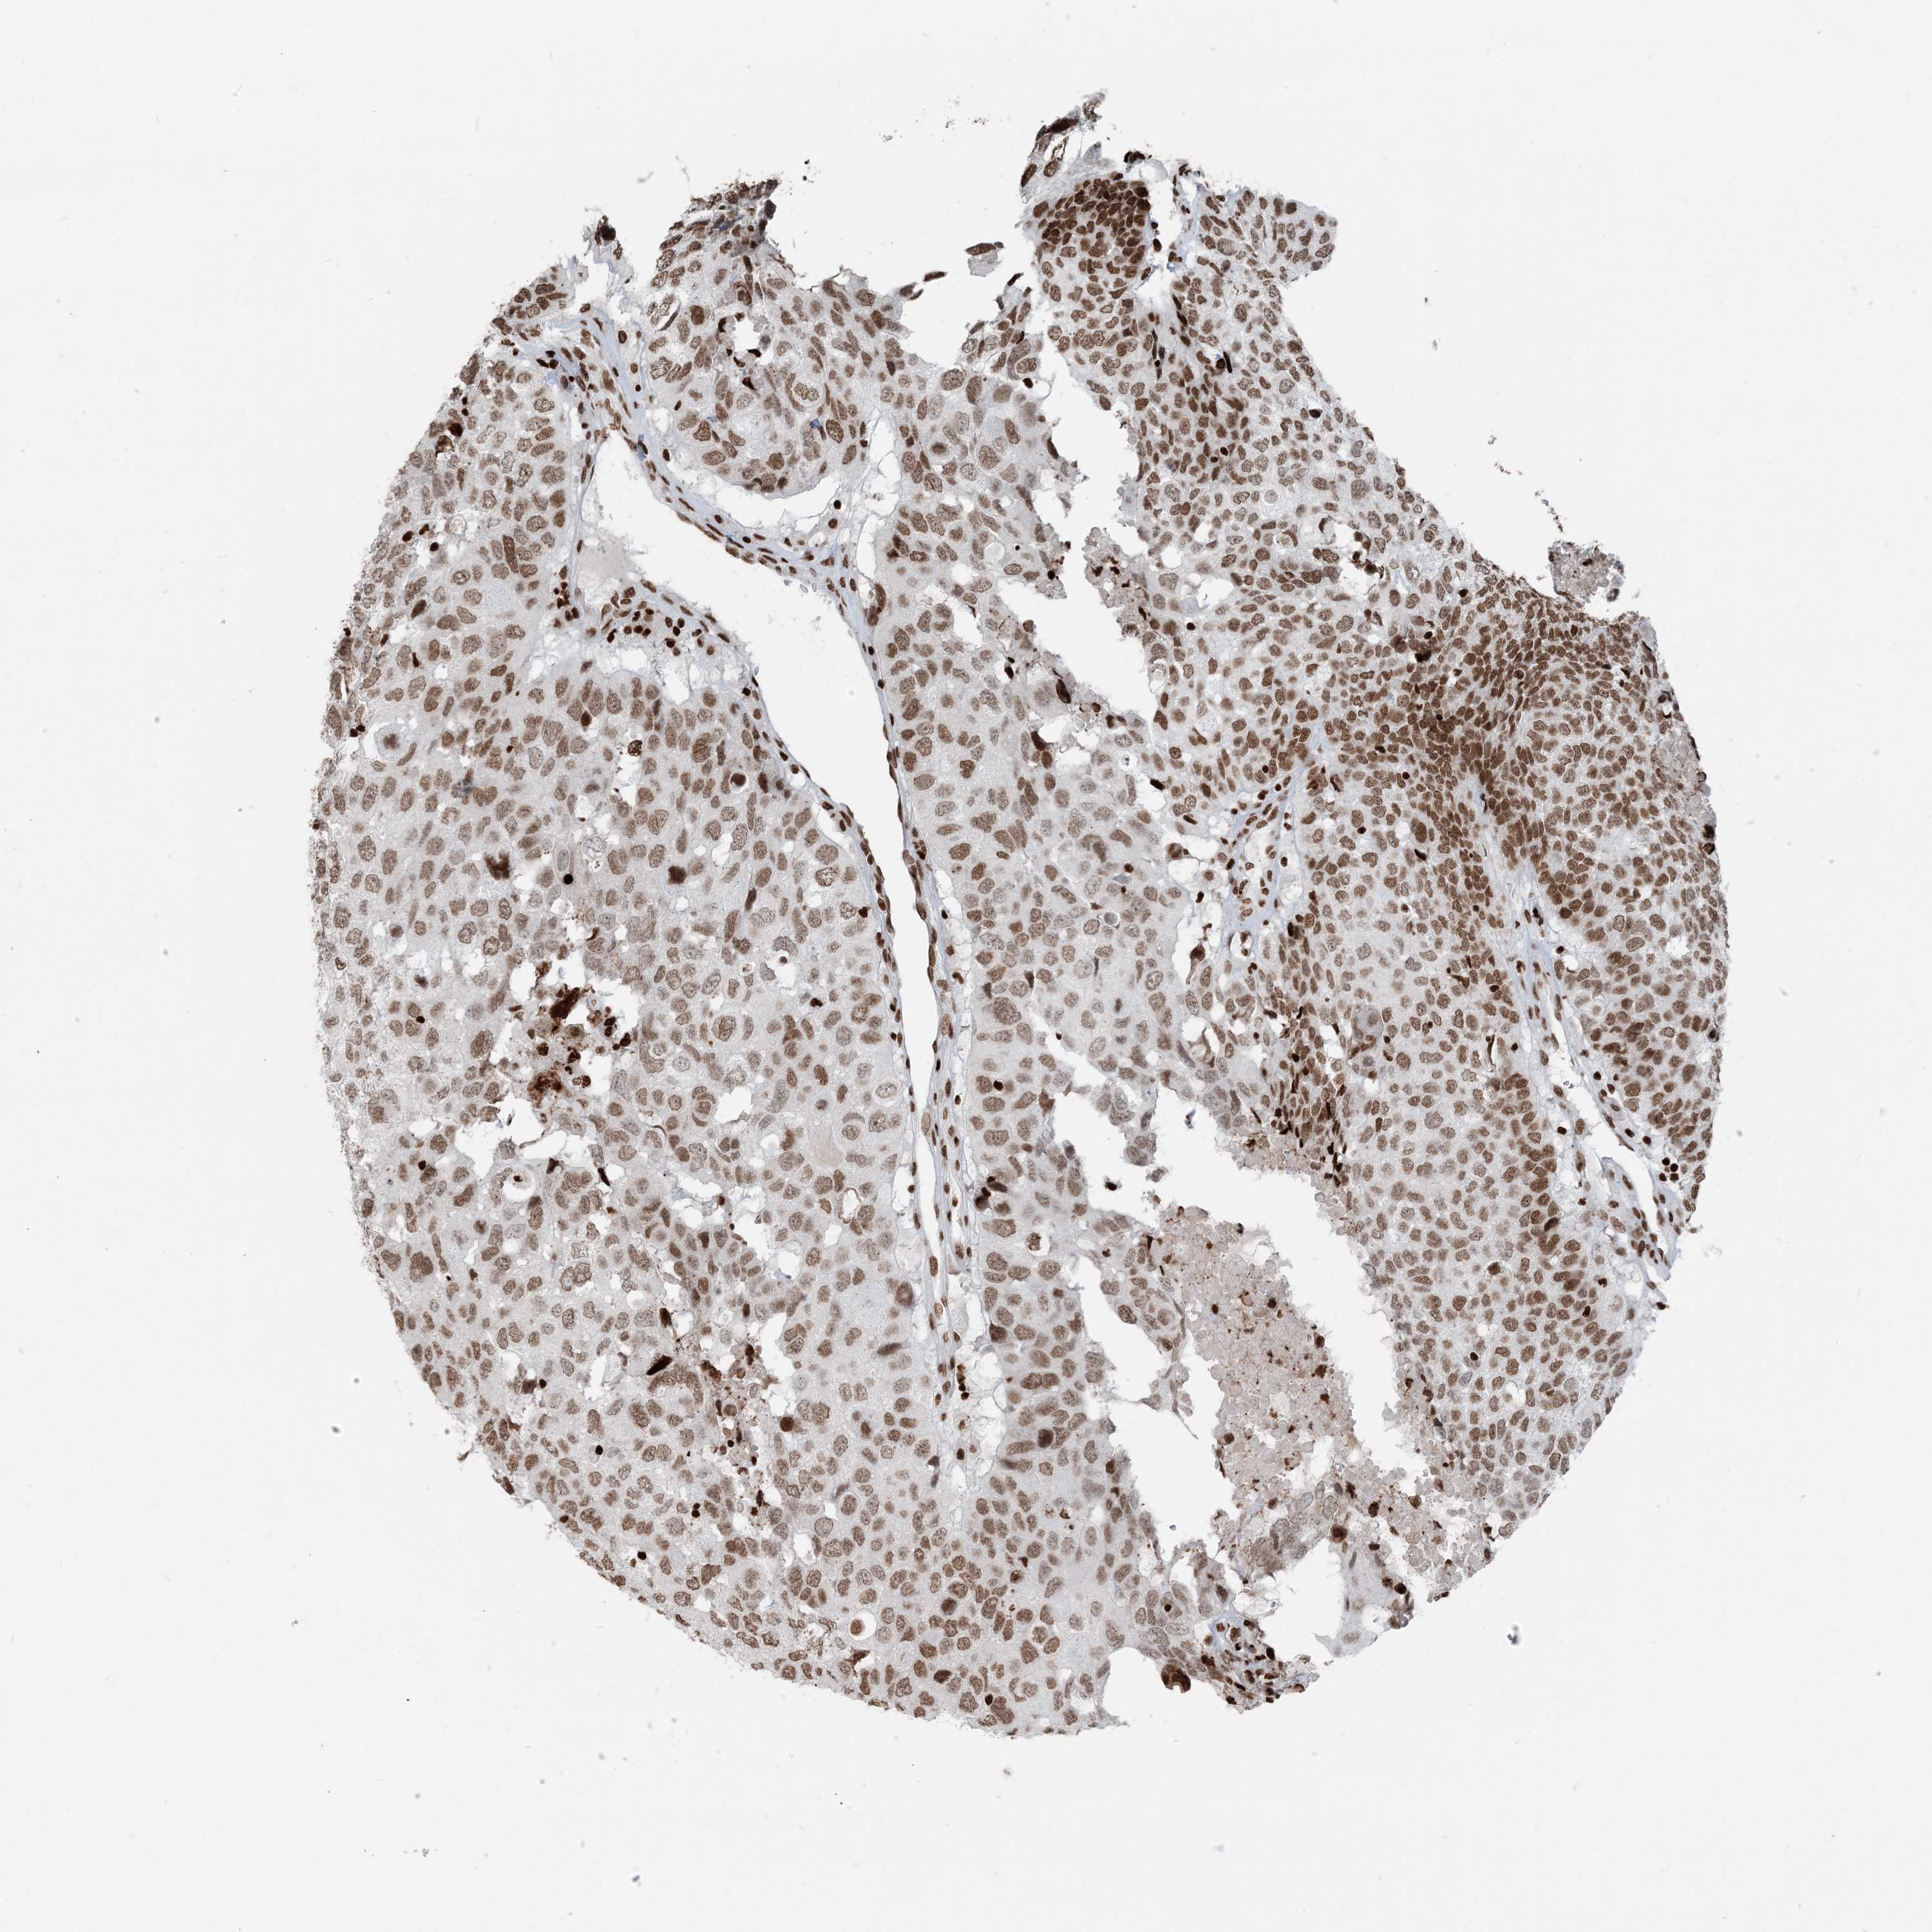

HEAD AND NECK CANCER - Protein expressioni

A mouse-over function shows sample information and annotation data. Click on an image to view it in a full screen mode. Samples can be filtered based on level of antibody staining by selecting one or several of the following categories: high, medium, low and not detected. The assay and annotation is described here.

Antibody stainingi

Antibody staining in the annotated cell types in the current human tissue is reported as not detected, low, medium, or high, based on conventional immunohistochemistry profiling in selected tissues. This score is based on the combination of the staining intensity and fraction of stained cells.

Each image is clickable and will lead to virtual microscopy that enables deeper exploration of all samples and also displays staining intensity scores, fraction scores and subcellular localization as well as patient and tissue information for each sample.

Antibody HPA042570

Antibody CAB037166

Antibody CAB037187

Antibody CAB037221

Staining

High

Medium

Low

Not detected

Intensity

Strong

Moderate

Weak

Negative

Quantity

>75%

75%-25%

<25%

None

Location

Nuclear

Cytoplasmic/membranous

Cytoplasmic/membranous,nuclear

Squamous cell carcinoma, NOS

Adenocarcinoma, NOS

Squamous cell carcinoma, metastatic, NOS

Adenoma, NOS